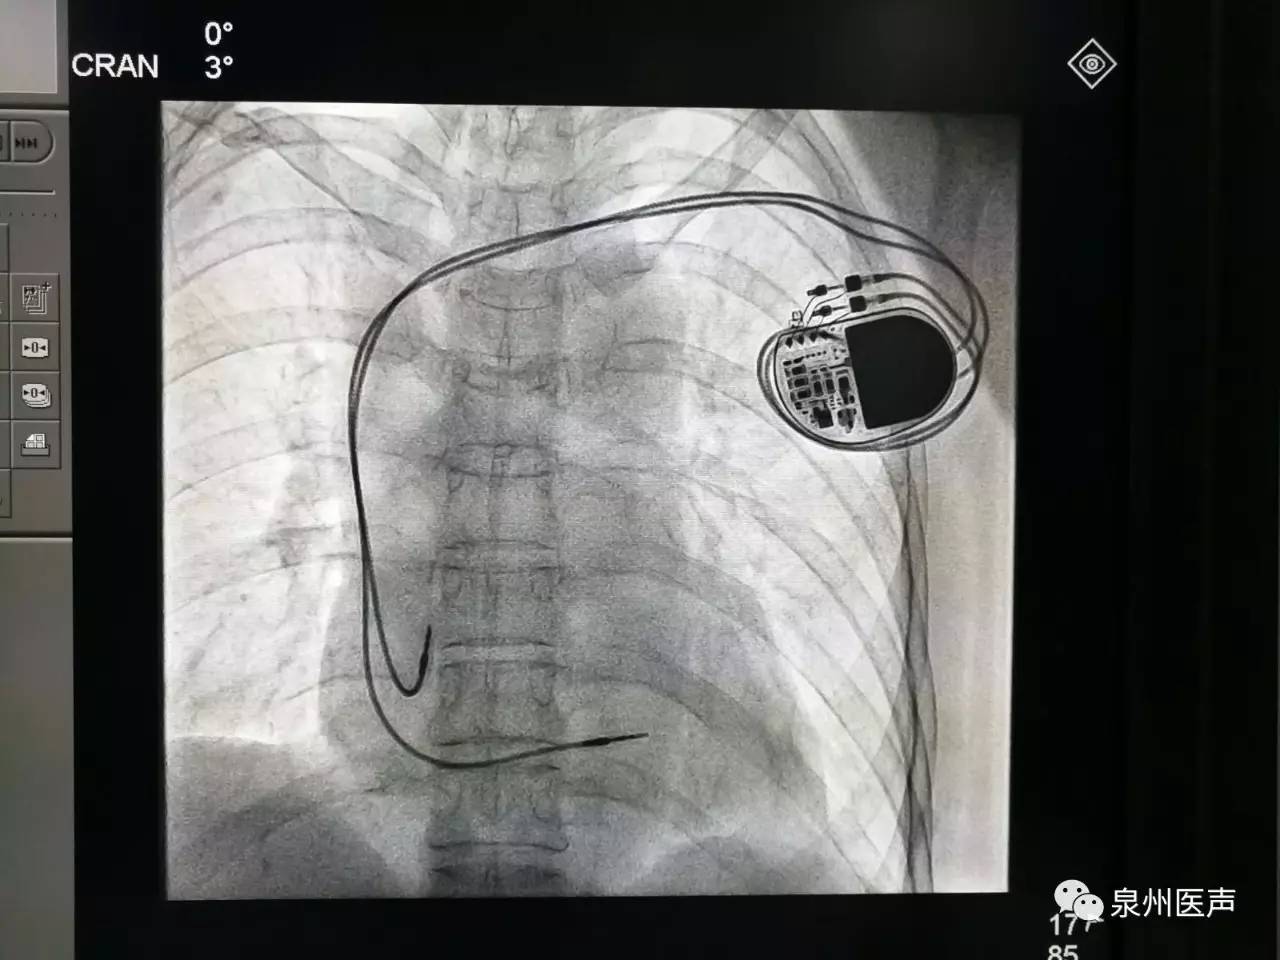

全球唯一!無(wú)線(xiàn)雙腔起搏器首次植入

來(lái)源:器械之家,未經(jīng)授權(quán)不得以任何形式轉(zhuǎn)載,且24小時(shí)后方可轉(zhuǎn)載。2022年2月7日雅培宣布,其在研型Aveir?雙腔無(wú)引線(xiàn)起搏器完成了全球首例患者植入,這也是全世界第一個(gè)雙腔無(wú)線(xiàn)起搏器。Aveir?DR雙腔起搏器提供右心房和心臟右心室的同步、逐次跳起搏,近80%接受起搏器治療的患者需要雙腔選擇,A